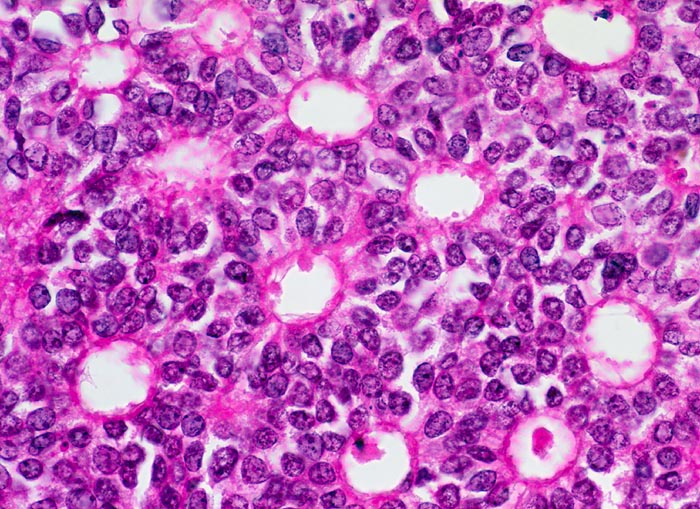

PathoPic – image database / PathoPic ID 5184 - Duktales carcinoma in situ, non high grade

Duktales carcinoma in situ, non high grade

Mamma

Monormorphe Tumorzellen mit runden hyperchromatischen Kernen bilden kribriforme Strukturen mit wie ausgestanzt wirkenden Löchern.

Invasiv duktales Mammakarzinom

400